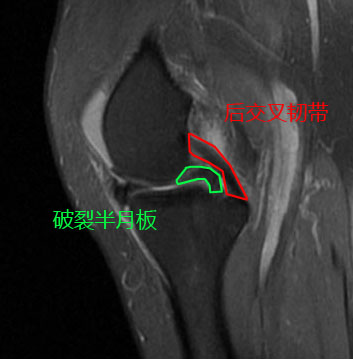

由于已经过去了4年没有再复查核磁,谢医生给她安排了核磁检查,在复查的过程当中我们可以看到非常好的一点是,经历了4年,她的关节软骨还真就没有被破裂的的半月板明显的磨损掉,但是桶柄状的撕裂,没有任何愈合的迹象,在核磁上我们仍然可以看到非常经典的双后交叉韧带征,这说明仍然有大部分的半月板撕裂后,卡在了关节腔内。

这种关节软骨保留得非常好,没有被破裂的半月板磨损的情况,非常适合进行关节镜手术治疗,经过关节镜的手术治疗,我们可以把破裂的半月板进行部分切除,或者是尝试进行缝合,患者的疼痛将会有明显的减轻,关节功能将会得到明显的改善。